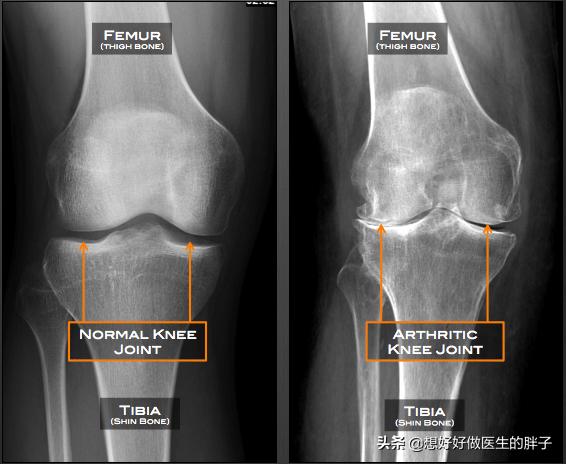

●Röntgenuntersuchung des KniegelenksMit der Röntgenaufnahme des Knies kann festgestellt werden, ob der Patient an einer signifikanten Osteoporose leidet und ob eine signifikante Verengung des Gelenkspalts vorliegt.OsteoarthritisIst die Existenz vonRheumatoide Arthritis.Oder ein anderes häufiges Knieproblem.

Wie Sie auf dem Bild unten sehen können, ist es typisch, dass sich die Gelenke entwickelt habenSichtbare Lücken, schmale Knochenbildung, einhergehend mit einer schwereren GelenkosteoporoseWenn ein solcher Patient offensichtliche Missempfindungen und Schmerzen hat, wird der Patient durch intraartikuläre Injektionen von Natriumvitrat oder ständige orale Analgetika, die dem Patienten nicht wirklich helfen, das Problem zu lösen, in starke Schmerzen versetzt.

- Frikativ--Wenn der Gelenkknorpel stark abgenutzt ist, verlieren die Enden der subchondralen Knochen den Knorpelschutz, und bei direkter Reibung ertönt ein leises, heiseres Reibegeräusch; die in der Gelenkhöhle umherwandernden Knorpeltrümmer verursachen auch leicht ein Einklemmen, was zu einem Gelenkreibungsgeräusch führt. Die Patienten sollten es von einem normalen physiologischen Knacken unterscheiden, das Beurteilungskriterium ist sehr einfach, ein pathologisches Knacken wird oft von Gelenkbeschwerden begleitet.